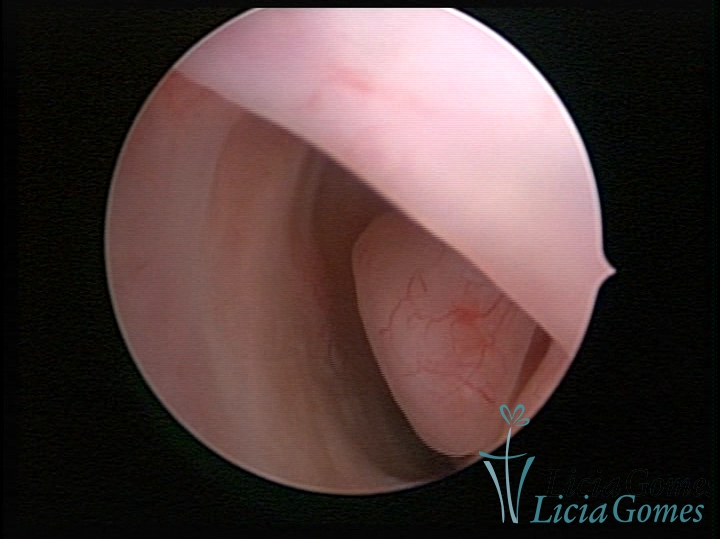

PÓLIPOS ENDOCERVICAIS

São tumores benignos, resultantes da proliferação focal reativa aos processos inflamatórios ou à situações de hiperestrogenismo, e podem ter sésseis (com a base de implantação larga) ou pediculados do epitélio.